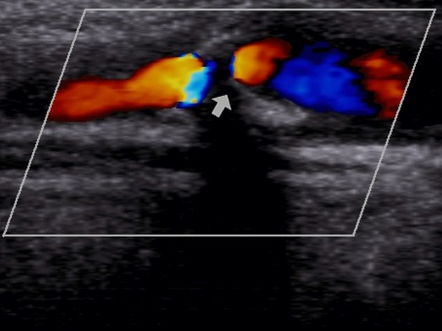

- 초음파의 색도플러·파워도플러 모드로 플라크 혈류와 내포된 출혈 여부를 평가할 수 있습니다.